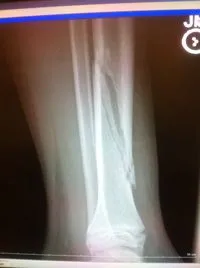

Pictured below is an x-ray of a more severe diaphyseal fracture of the tibia from higher velocity impact. This can heal without surgery but must be carefully monitored with above the knee casting to eliminate tibial torsional force from the knee or ankle.